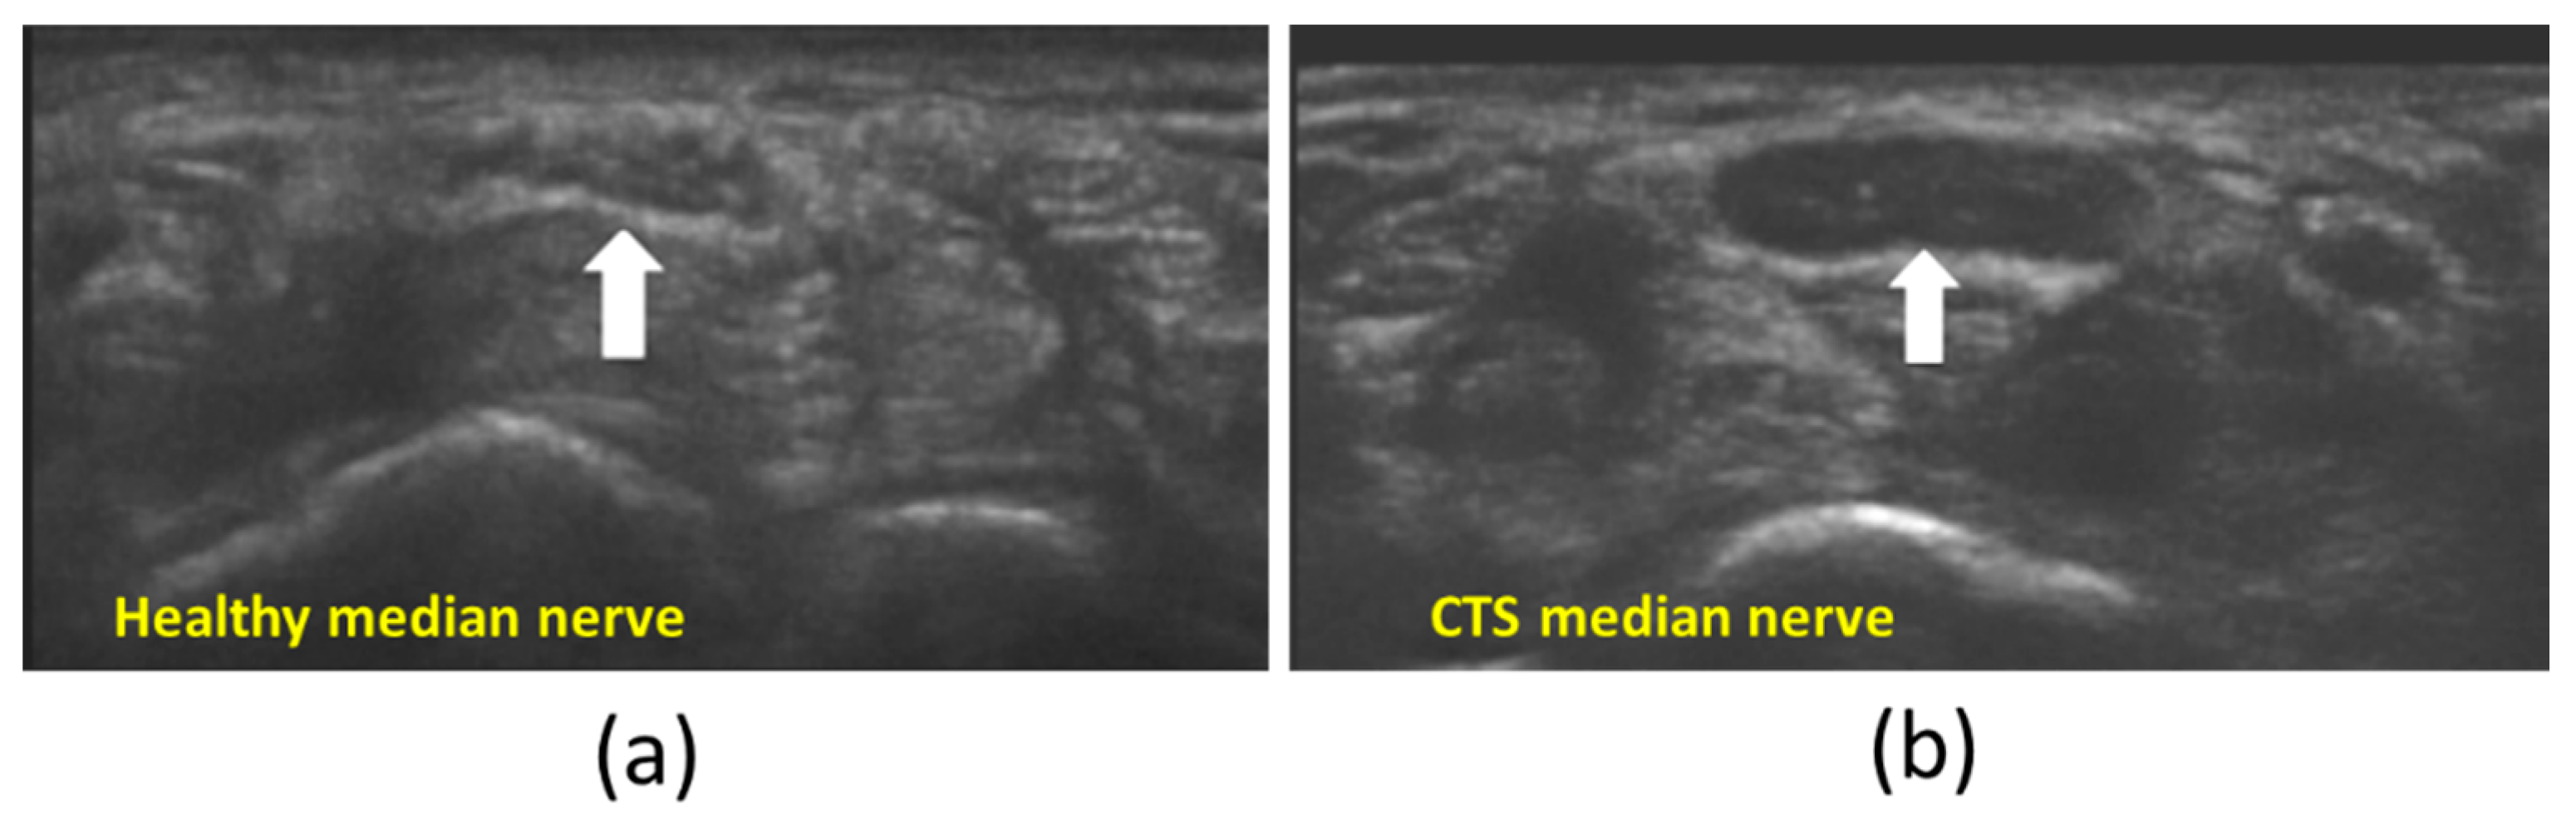

- Byra, M.; Hentzen, E.; Du, J.; Andre, M.; Chang, E.Y.; Shah, S. Assessing the Performance of Morphologic and Echogenic Features in Median Nerve Ultrasound for Carpal Tunnel Syndrome Diagnosis. J. Ultrasound Med. 2020, 39, 1165–1174. [Google Scholar] [CrossRef] [PubMed]

- Fu, T.; Cao, M.; Liu, F.; Zhu, J.; Ye, D.; Feng, X.; Xu, Y.; Wang, G.; Bai, Y. Carpal Tunnel Syndrome Assessment with Ultrasonography: Value of Inlet-to-Outlet Median Nerve Area Ratio in Patients versus Healthy Volunteers. PLoS ONE 2015, 10, e0116777. [Google Scholar] [CrossRef] [PubMed]